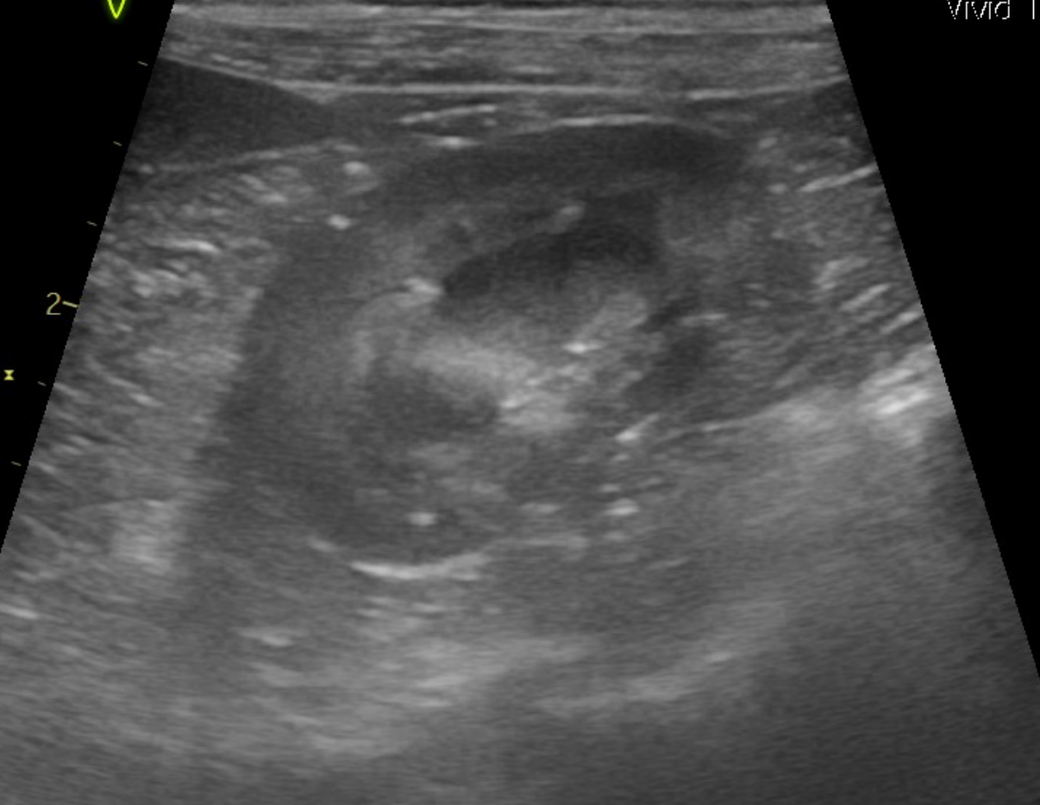

강아지 신장결석 종류 모양만으로는 판단이 안되나요? 소변에선 크리스탈이 발견된게 없다고 합니다

모양만으로 추측 조차 할수가 없는건가요? 한번 봐주시면 감사하겠습니다.

예, 없습니다. 결석이 매우 커진 상태 (몇센치미터 크기 정도)로 커졌을때나 일부 추정되지만 겉면과 내부 코어의 씨앗의 성분은 별도라 이때는 또 성분검사를 해야 하는정도로 부정확합니다.